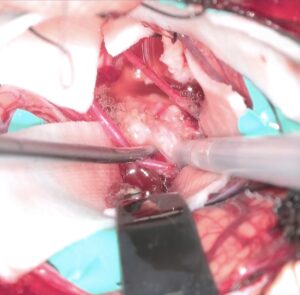

右嗅神経を剥離固定して右前頭葉だけを牽引して大脳半球間裂を剥離。

半球間裂の癒着が少なく、atraumaticに綺麗に開けることができました。

両側のGyrus rectusを剥離、前頭底にいたり、視神経と下垂体茎が見えます。

Trans-lamina terminalis approach、何度もやった古典的なアプローチです。A2と伴奏し縦走する視床下部動脈を温存して、その間隙から腫瘍を減圧していきます。